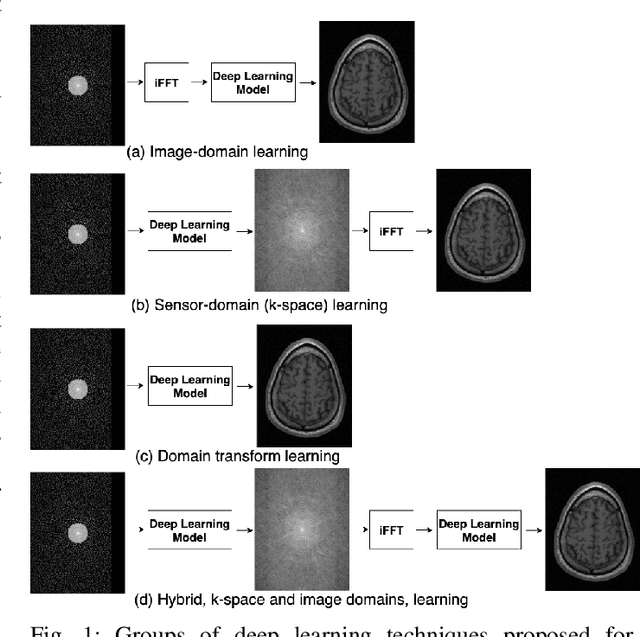

Abstract:The U-net is a deep-learning network model that has been used to solve a number of inverse problems. In this work, the concatenation of two-element U-nets, termed the W-net, operating in k-space (K) and image (I) domains, were evaluated for multi-channel magnetic resonance (MR) image reconstruction. The two element network combinations were evaluated for the four possible image-k-space domain configurations: a) W-net II, b) W-net KK, c) W-net IK, and d) W-net KI were evaluated. Selected promising four element networks (WW-nets) were also examined. Two configurations of each network were compared: 1) Each coil channel processed independently, and 2) all channels processed simultaneously. One hundred and eleven volumetric, T1-weighted, 12-channel coil k-space datasets were used in the experiments. Normalized root mean squared error, peak signal to noise ratio, visual information fidelity and visual inspection were used to assess the reconstructed images against the fully sampled reference images. Our results indicated that networks that operate solely in the image domain are better suited when processing individual channels of multi-channel data independently. Dual domain methods are more advantageous when simultaneously reconstructing all channels of multi-channel data. Also, the appropriate cascade of U-nets compared favorably (p < 0.01) to the previously published, state-of-the-art Deep Cascade model in in three out of four experiments.